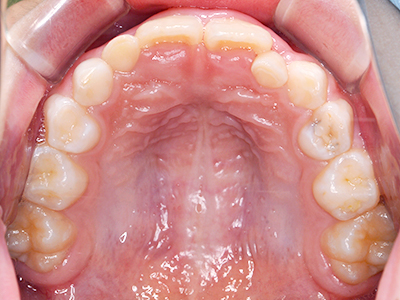

歯並びの相談に来られるお子様は、口呼吸をしているケースが多く、これが歯並びに大きな影響を与えています。

↓ - 頬の圧力が上の歯列にかかりやすくなる

↓ - 上あごが狭くなる

ないき歯科クリニックでは、上あごの成長不足を補い、鼻呼吸を獲得しつつ歯列を整え、将来のお口をより健康な状態にすることをゴールに定める矯正治療をおこなっています。